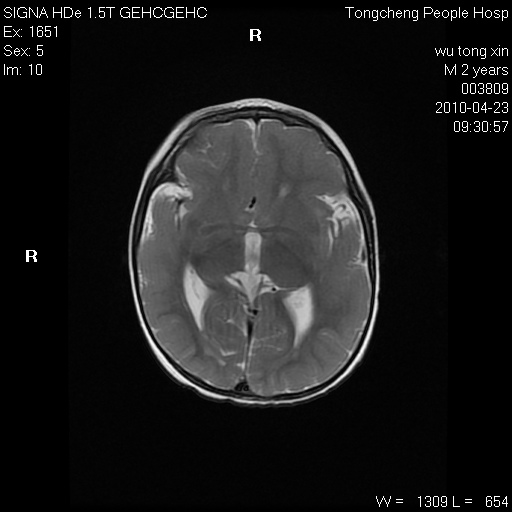

以下是引用赵物学在2010-4-25 12:43:00的发言:[br]巨脑回[br]侧脑室后角低密度影考虑hie或肾上腺脑白质营养不良?[br][br][本贴已被 赵物学 于 2010-4-25 12:51:28 修改过]

以下是引用gaoxiao在2010-4-25 16:54:00的发言:[br]巨脑回畸形。脑白质髓鞘化不良

以下是引用pujunzhi在2010-4-25 21:35:00的发言:[br]考虑 1双侧大脑皮质发育不良 2轻度脑积水 3双侧脑室后角旁片状长t1长t2信号,需继续观察,因为正常小儿此处脑白质的髓鞘化时间可以延迟到4-6岁,才显示正常。